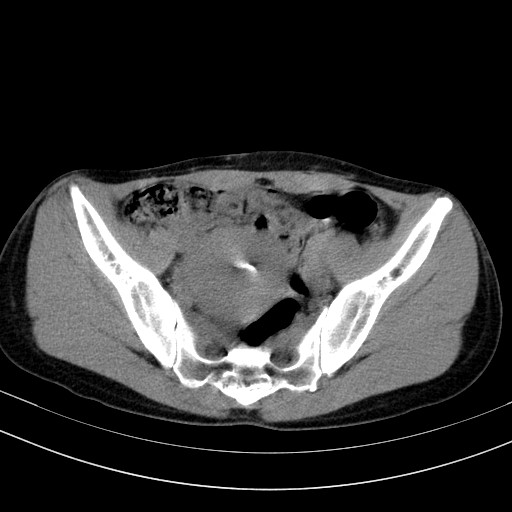

以下是引用随光逐影在2009-4-7 8:17:00的发言:[br]考虑宫颈占位性病变(宫颈癌?);建议行进一步检查。

以下是引用jiangjing在2009-4-7 16:46:00的发言:[br]宫颈增大,结构不清,右侧附件区可疑囊样占位,建议增强及mri 检查